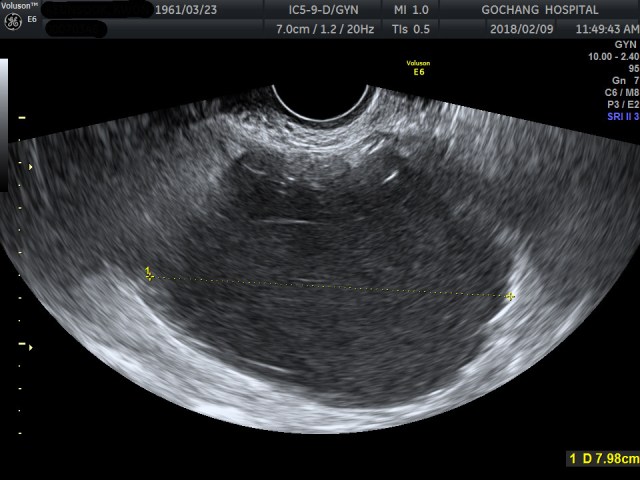

56세 여자 환자분이고, 위의 초음파영상은 산부인과에서 시행한 질초음파영상입니다. 크기가 매우 큰 낭성병변을 발견하고, 이를 감별하기 위해 CT를 영상의학과에 의뢰하였습니다.

해당 낭성병변 외에도 우측 adnexa 부위에 작은 단순낭종과 uterine myoma병변도 같이 발견한 상태였습니다.

여기까지 봐도 질초음파영상에서 봤던 크기가 큰 낭성병변이 CT에서는 보이지 않았기에 방광을 낭성병변으로 본 게 아닌가 하는 의심을 가지고, 다시 질초음파 및 복부초음파를 시행했지만, 여전히 위에서 보여준 커다란 낭성병변이 존재하고, 소변을 다 본 상태에서도 전혀 변함없이 병변이 확인되는 거였습니다.

두번째 시행했던 초음파영상에서도 낭성병변이 여전히 확인되는 것을 보고, 제가 CT에서 뚜렷이 보였던 dermoid cyst가 있었다는 걸 뒤늦게 발견한 사례입니다. 지금 보면 정말 황당하고 썰렁한 실수였지만, 영상의 질이 제대로 확보된 질초음파영상에서 소변으로 가득찬 방광과 dermoid cyst는 쉽게 구별이 가능하다는 점을 생각하고 처음에 산부인과에서 촬영했던 질초음파영상을 좀 더 주의깊게 봤었다면 CT를 판독하면서 쓸데없는 수고와 위험을 초래하지 않았을 것입니다.